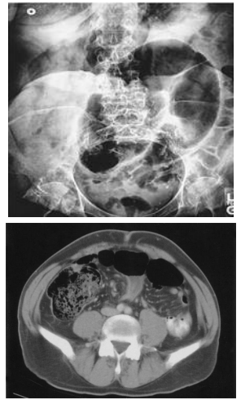

“Paciente J.A.B, masculino, 64 anos, deu entrada no Pronto Socorro com queixa de dor abdominal súbita há mais ou menos 6 horas, do tipo em cólicas em andar inferior do abdome, com distensão quase imediata. Associado, refere parada de eliminação de gases e fezes e dois episódios de vômitos com conteúdo alimentar. Nega cirurgias prévias e quadros semelhantes anteriormente. Ao exame físico apresentava-se em bom estado geral, a não ser fácies de dor, gemente, corado, levemente desidratado, frequência cardíaca de 118 batimentos por minuto e abdome globoso, distendido com ruídos hidroaéreos diminuídos, doloroso à palpação difusamente com mais intensidade em baixo ventre e hipertimpânico à percussão. Realizou radiografia simples de abdome, tomografia de abdome e radiografia de clister opaco demonstrados abaixo respectivamente”.